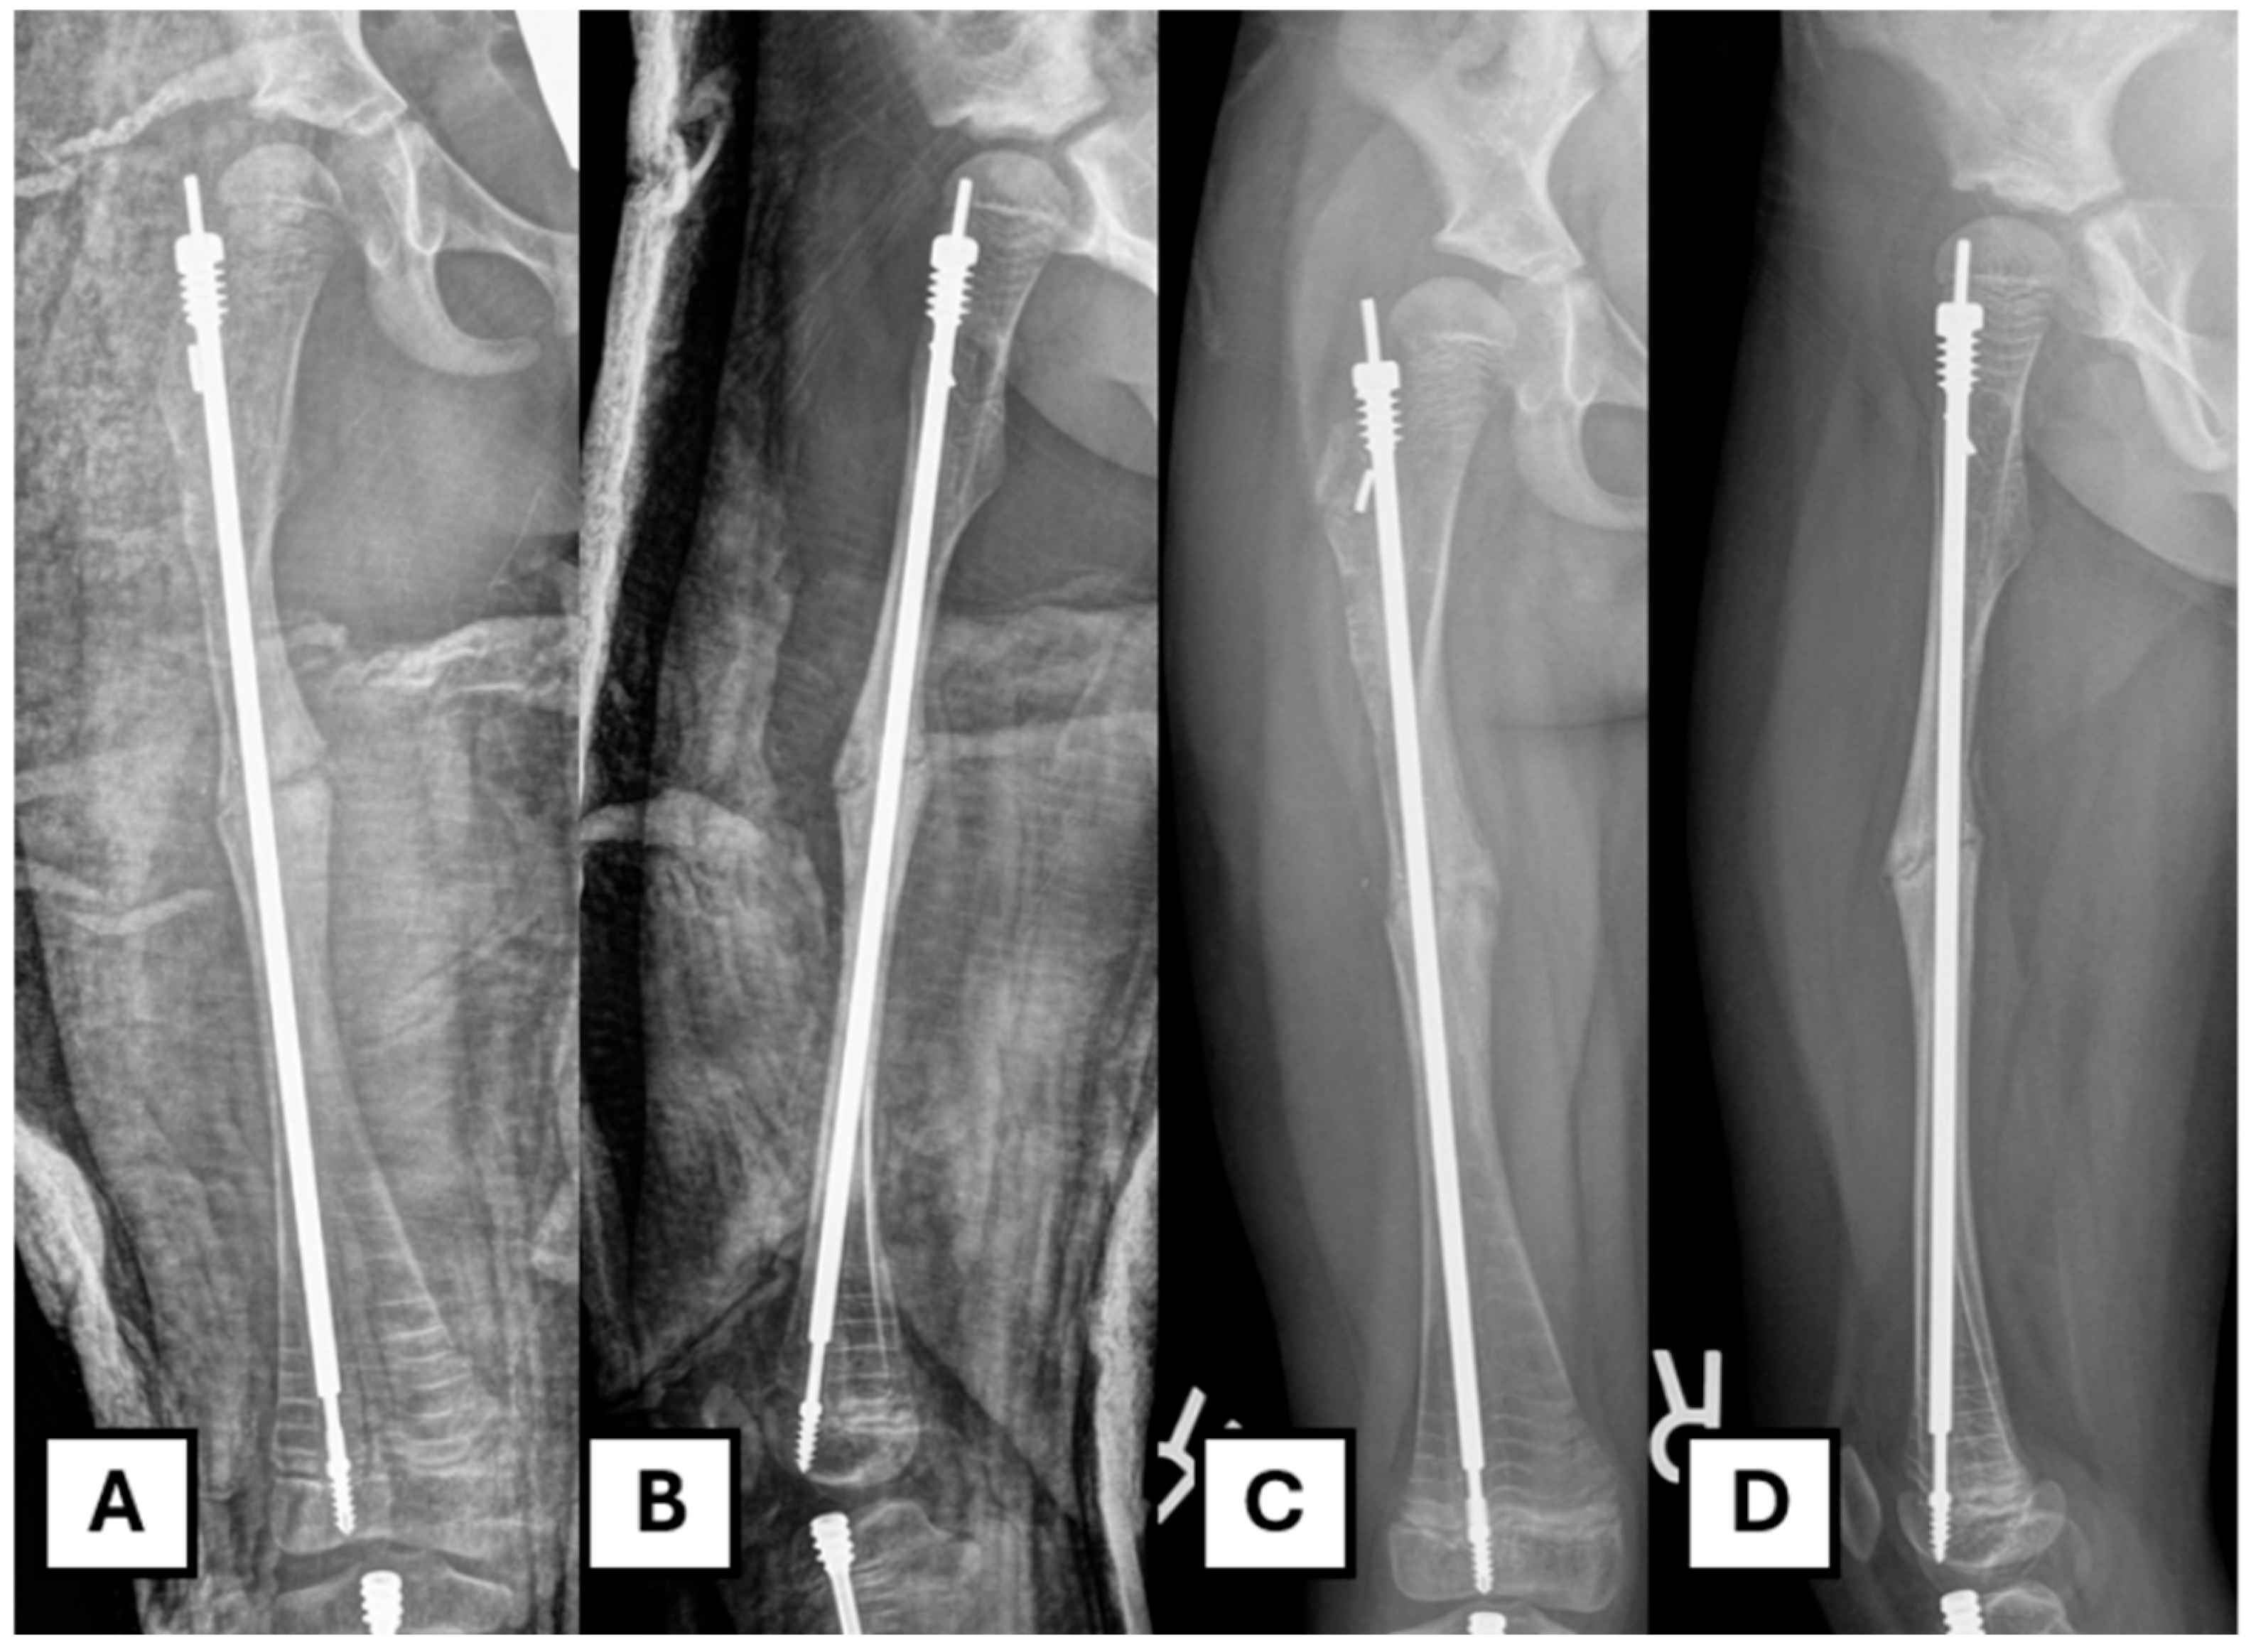

To conserve as much bone as possible and avoid coring out the head of the female component, a retrograde approach is undertaken. A suitable trephine with an appropriate diameter (e.g., 7 mm for a 3.2 mm rod) and length is placed coaxially over the end of the female component. In this case, the FD trephine of an appropriate size was missing from the rescue set; therefore, we needed to use a separate trephine (7 mm inner diameter and a thickness of 1 mm). The surrounding bone is then removed along the extent of the rod as far as the proximal fixation (Figure 3A–E).

Using a trephine that passes over the female component provides more control and limits unnecessary bone loss, ensuring that the majority of bone loss occurs ideally within the canal. Prudent use of fluoroscopy is employed throughout this process to avoid unnecessary bone removal.

Figure 3. The retrograde trephine technique for implant removal. (A) Illustration of the trephine being placed over the migrated female component. The red dotted area shows the bone to be removed (B,C) The trephine advances over the rod, removing bone from within the canal, as shown in the illustration and corresponding radiograph. (D,E) Further advancement of the trephine towards the proximal fixation, confirmed by fluoroscopy.